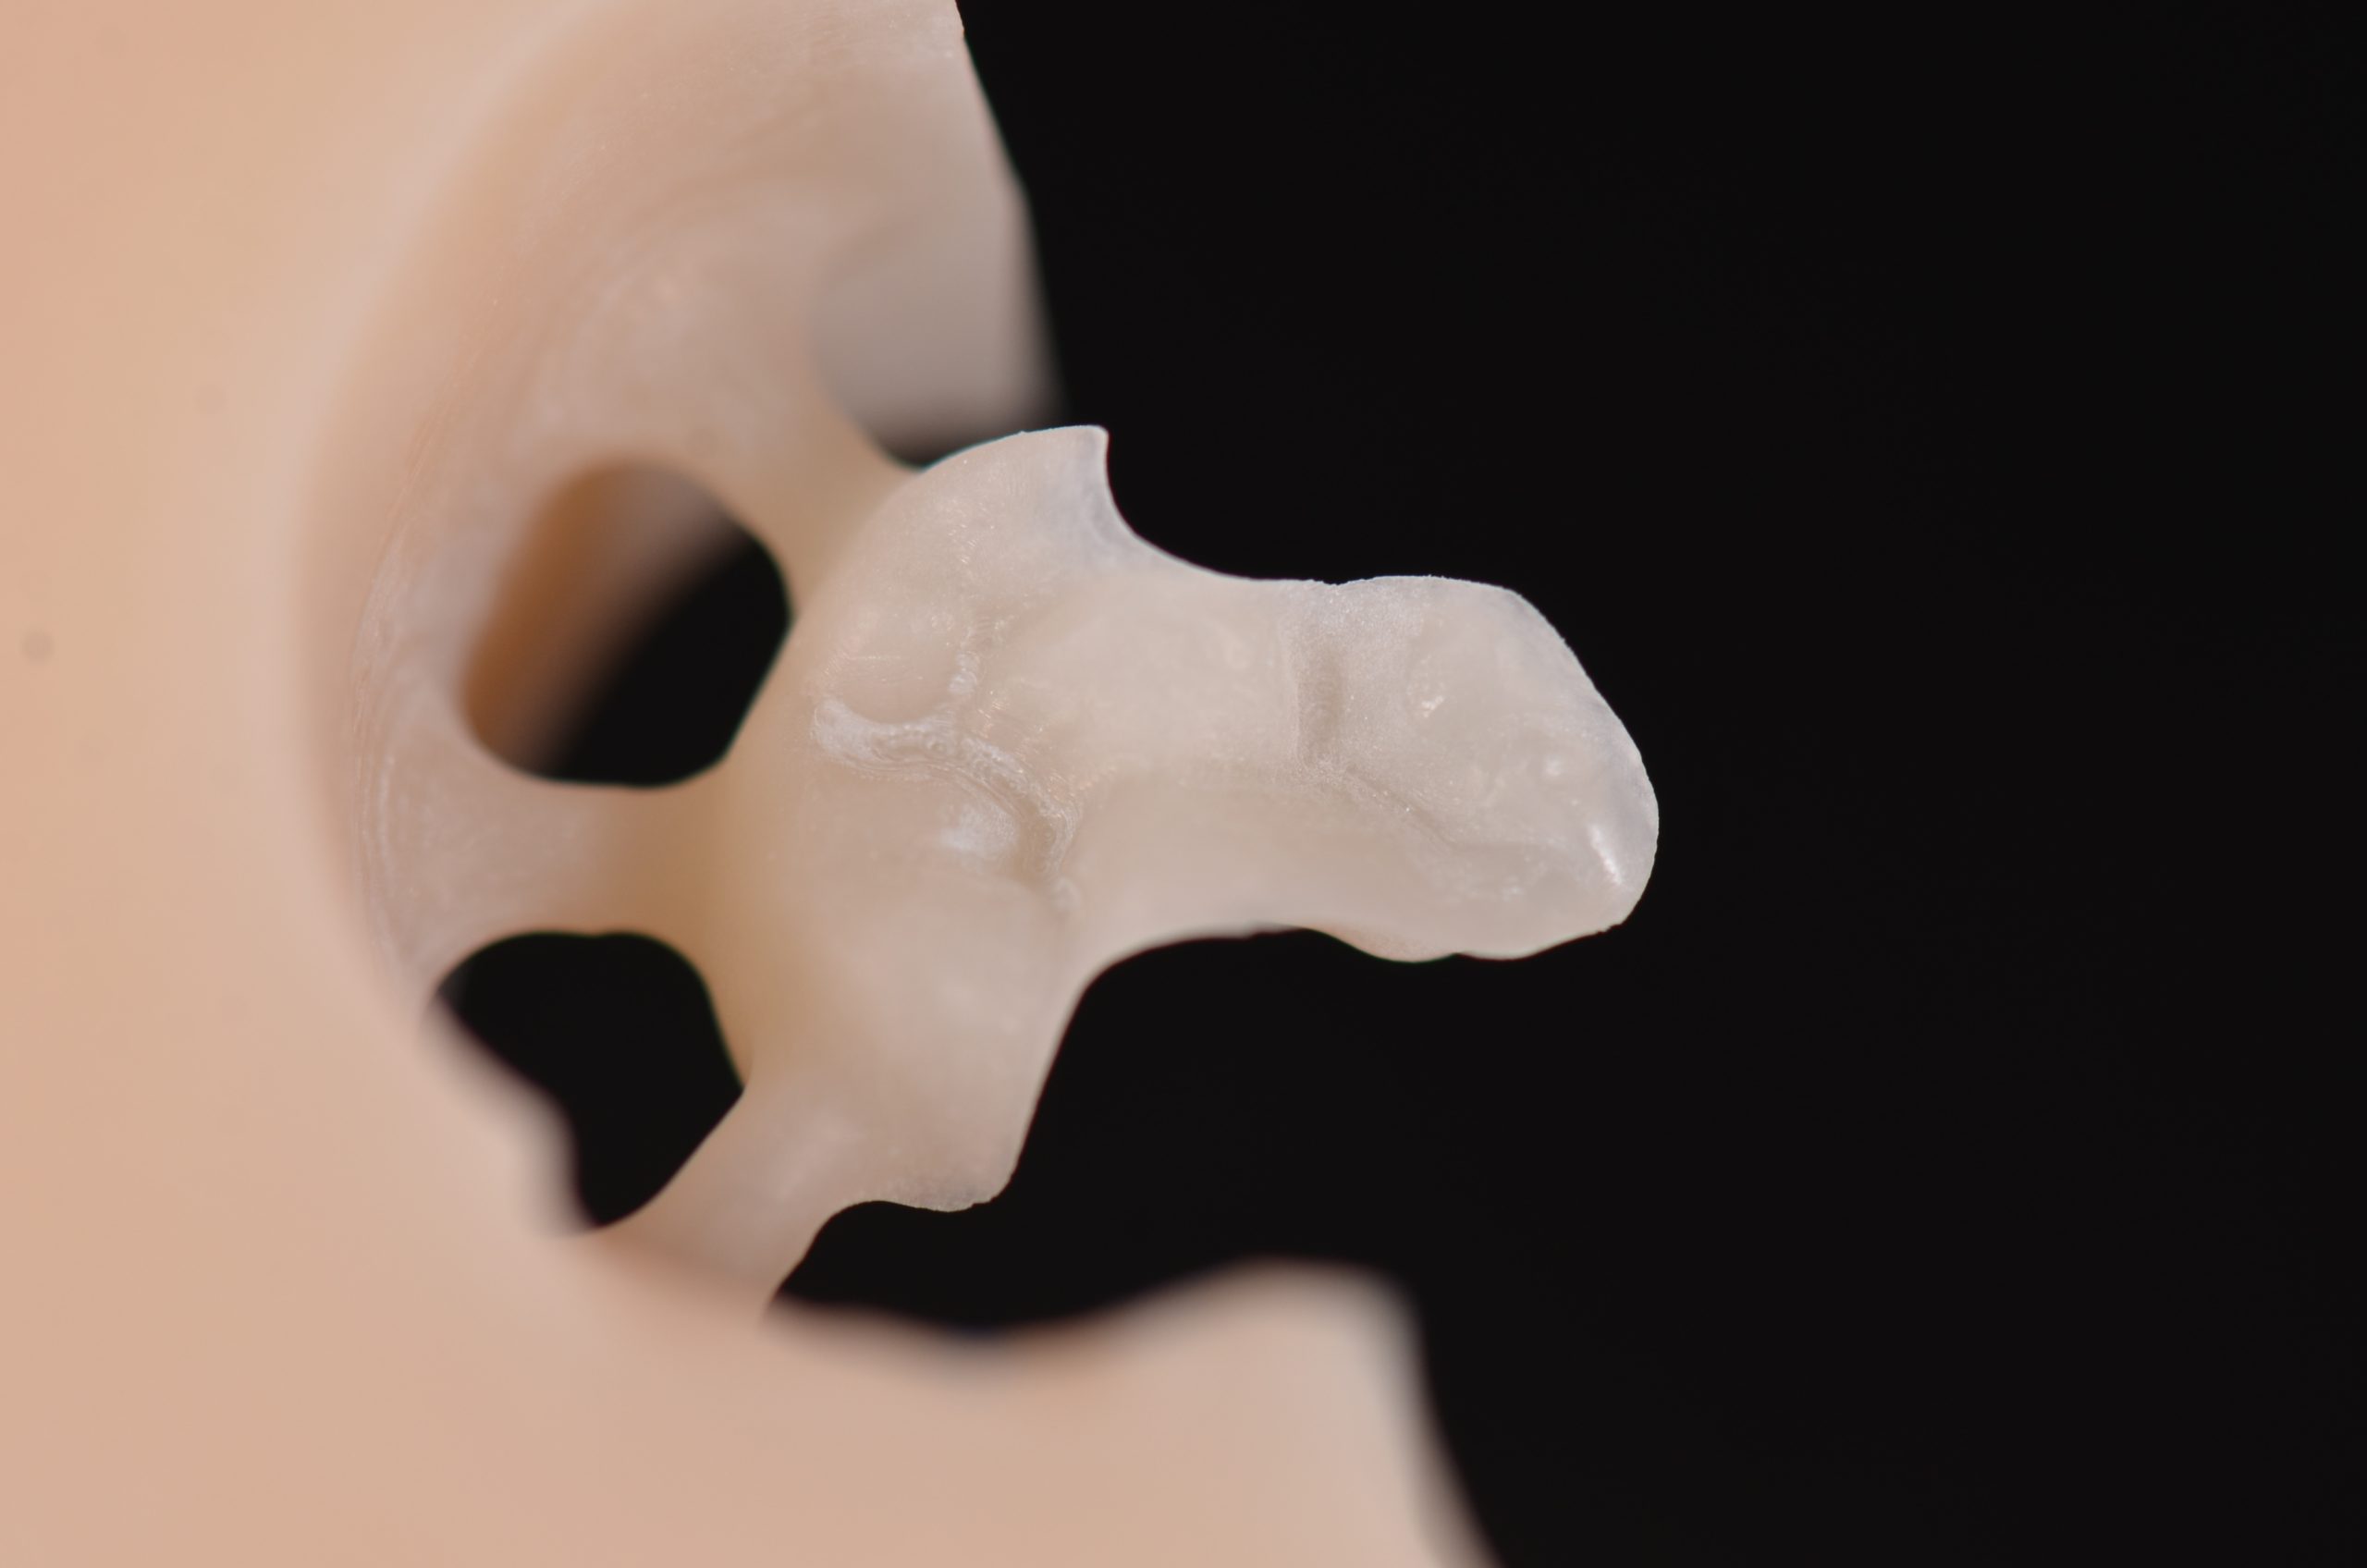

Per la realizzazione del restauro, l’odontotecnico effettua due colate delle impronte: la prima con gesso superduro, la seconda con gesso universale bianco.

I modelli ottenuti vengono scansionati e trasformati in file STL, poi inviati al laboratorio odontotecnico per la progettazione digitale. Il software consente la visualizzazione dei modelli virtuali e la modifica dei monconi sfilabili. Dopo la selezione del materiale, si procede con una ceratura digitale che tiene conto dei sottosquadri, dello spazio cementizio (70 μm), delle linee di finitura della preparazione e dello spessore minimo dei margini del restauro. Dopo 20–40 minuti di lavorazione, l’onlay viene fresato. Il restauro viene quindi separato dal blocchetto mediante uno strumento rotante, rifinito e adattato sui modelli (11-13) (Figure 10-11).

Sul modello sezionato in gesso superduro, il moncone dell’elemento 1.6 è rimovibile: questo consente di definire con precisione sia i contorni sia l’articolazione verticale dell’onlay. Il modello in gesso universale, più preciso, viene utilizzato come modello di studio, per controllare accuratamente il fitting interprossimale del restauro (Figure 12a-b).

La procedura si conclude con la rifinitura e lucidatura del restauro, precedute da pulizia e disinfezione con alcool.